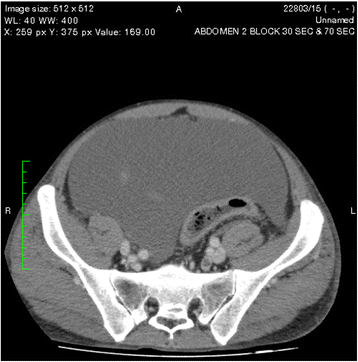

One of the pseudocysts in the head of the pancreas was compressing the inferior vena cava (IVC), as shown in the CECT scans in Figs. 2, 3 and 4. There were filling defects in the left common and internal iliac veins and both proximal external iliac veins, suggesting DVT (Figs. 5 and 6). The patient’s IVC was patent. Multiple filling defects were seen in the right lower lobe pulmonary artery and in segmental branches of the left pulmonary artery, compatible with pulmonary embolism (Figs. 7 and 8). The patient’s liver, gallbladder, spleen, kidneys, and adrenal glands were normal. He had bilateral atelectasis of the lung bases with minimal pleural effusions.

Vascular complications of pancreatitis are a major cause of morbidity and mortality. Venous complications are predominantly related to splanchnic vein thrombosis due to local inflammation [1]. Pulmonary embolism is a rare complication of pancreatitis that has been described in few case reports [7]. Renal vein and IVC thrombosis associated with acute pancreatitis has been reported [8]. DVT and hypercoagulable states in pancreatitis are thought to be due to release of pancreatic proteolytic enzymes from a cyst that is connected to the pancreatic duct and penetrates into a vessel. The pancreatic juice triggers the formation of a thrombus secondary to vasculitis. Proteolytic damage or inflammation of the vessels may also play a significant part, and pancreatic elastase has been shown to play a major role in the development of pulmonary vascular injury after acute pancreatitis [9]. It is also thought that hypercoagulability in pancreatitis is due to a combination of hepatic dysfunction and hypertrypsinemia (resulting in raised fibrinogen and factor VIII concentrations) and cachexia. Acute pancreatitis provokes deleterious effects in the endothelium-dependent relaxing response for acetylcholine in mesenteric rings that are strongly associated with high plasma nitrite/nitrate levels as a consequence of intense inflammatory responses. Furthermore, the subsensitivity of the contractile response to phenylephrine in both mesenteric and pulmonary rings might be due to the complications of this pathological condition in the early stage of pancreatitis [10]. In DVT, immobility may also contribute. In our patient, one of the pancreatic pseudocysts was compressing the IVC, as shown on CECT of the abdomen, although direct communication was not seen.